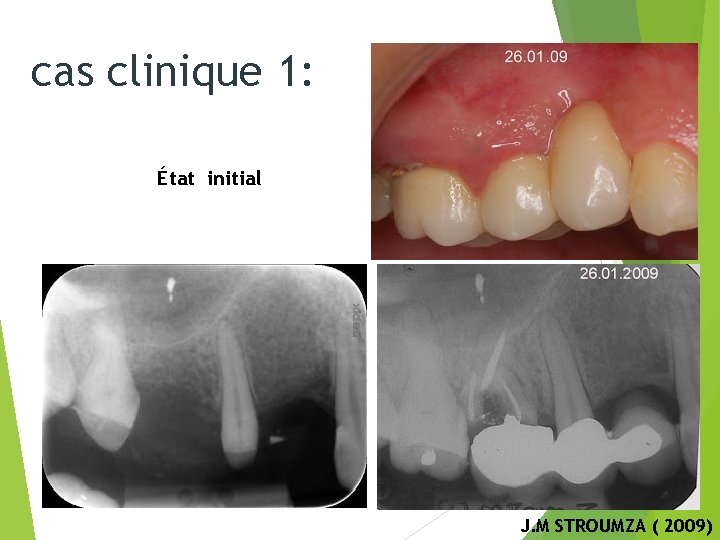

cas clinique 1: État initial Radio pré-opératoire J. M STROUMZA ( 2009)